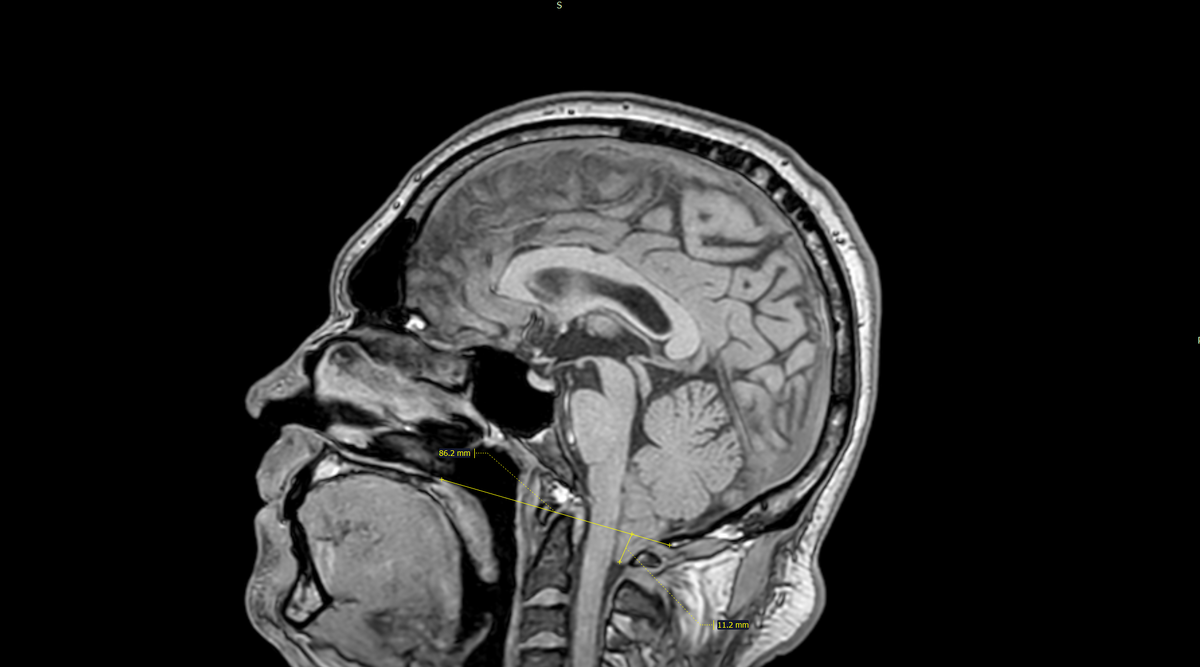

Аномалия(мальформация) Арнольда-Киари 1(первого) типа

Это врожденное заболевание, при котором часть мозжечка (миндалины мозжечка) смещается вниз через большое затылочное отверстие (foramen magnum) в позвоночный канал. Это может приводить к сдавлению ствола головного мозга, нарушению циркуляции спинномозговой жидкости (ликвора) и появлению неврологических симптомов. Симптомы аномалии Арнольда-Киари I типа могут варьироваться в зависимости от степени смещения и сдавления структур мозга. У некоторых пациентов заболевание протекает бессимптомно и обнаруживается случайно при обследовании. Возможные симптомы включают: Лечение зависит от выраженности симптомов: Прогноз зависит от степени выраженности аномалии и своевременности лечения. При своевременной диагностике и адекватном лечении (особенно хирургическом) возможно значительное улучшение состояния и устранение симптомов. Однако в некоторых случаях симптомы могут сохраняться или прогрессировать. Смещение миндалин мозжечка ниже линии Чемберлена на 11мм.Заключение:Аномалия Арнольда-Киари 1 тип

Смещение миндалин мозжечка ниже линии Чемберлена на 11мм.Заключение:Аномалия Арнольда-Киари 1 типа.